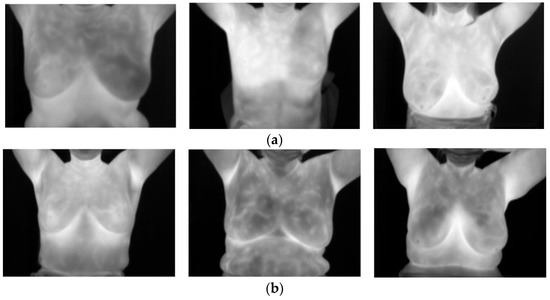

A summary of the consolidated dataset is given in Table 1, and the sample grayscale thermal images are given in Figure 4.

Figure 4.

Sample thermal images of breasts from the dataset: (a) sick (Hospital of Nur-Sultan), (b) healthy (Hospital of Nur-Sultan), (c) sick (DMR), and (d) healthy (DMR).

The combined dataset consisted of a total of 306 images; 123 thermal images of patients classified as “sick” (as indicated in the doctor’s diagnosis report), and 183 thermal images classified as “healthy”. Patients’ thermographic images classified as “healthy” represented that the patient was not diagnosed with having tumors or any cancerous cells in the breast area. If the thermograms were labeled as “sick,” the patient had a tumor. It may have been either malignant or benign. The dataset was be divided into three sets dedicated to training, cross-validation, and testing purposes. Table 2 reveals the details of our final training and testing sets.